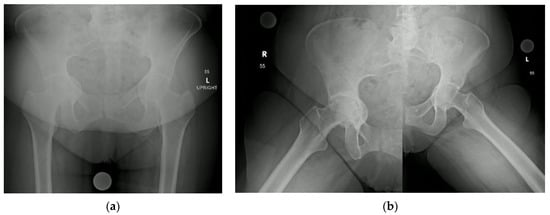

| Class | Ilioischial Line | Iliopectineal Line | Recommended Treatment |

|---|---|---|---|

| I | Intact (femoral head medialized) | Intact | Implant Placement: Lateralization of acetabular component to match native rim. Standard component needed, no need for screw augmentation. Bone graft: Not likely required. |

| II | Violated | Intact | Implant Placement: Lateralization of acetabular component to rim, consider use of larger or jumbo component. Screw fixation optional. Consider lateralized acetabular liner. Bone Graft: Likely required medially with impaction grafting. |

| III | Violated | Violated | Implant Placement: Lateralization of acetabular component, consider use of jumbo, deep profile, revision, or multi-hole component. Screw fixation is strongly recommended in multiple planes to augment construct stability. Consider lateralized acetabular liner. Bone Graft: Universally required. Autograft reamings and morselized cortical bone from native head is recommended, consider use of additional allograft bone to fill large defects. Powdered antibiotic can be added to graft mixture to reduce risk of prosthetic joint infection. |